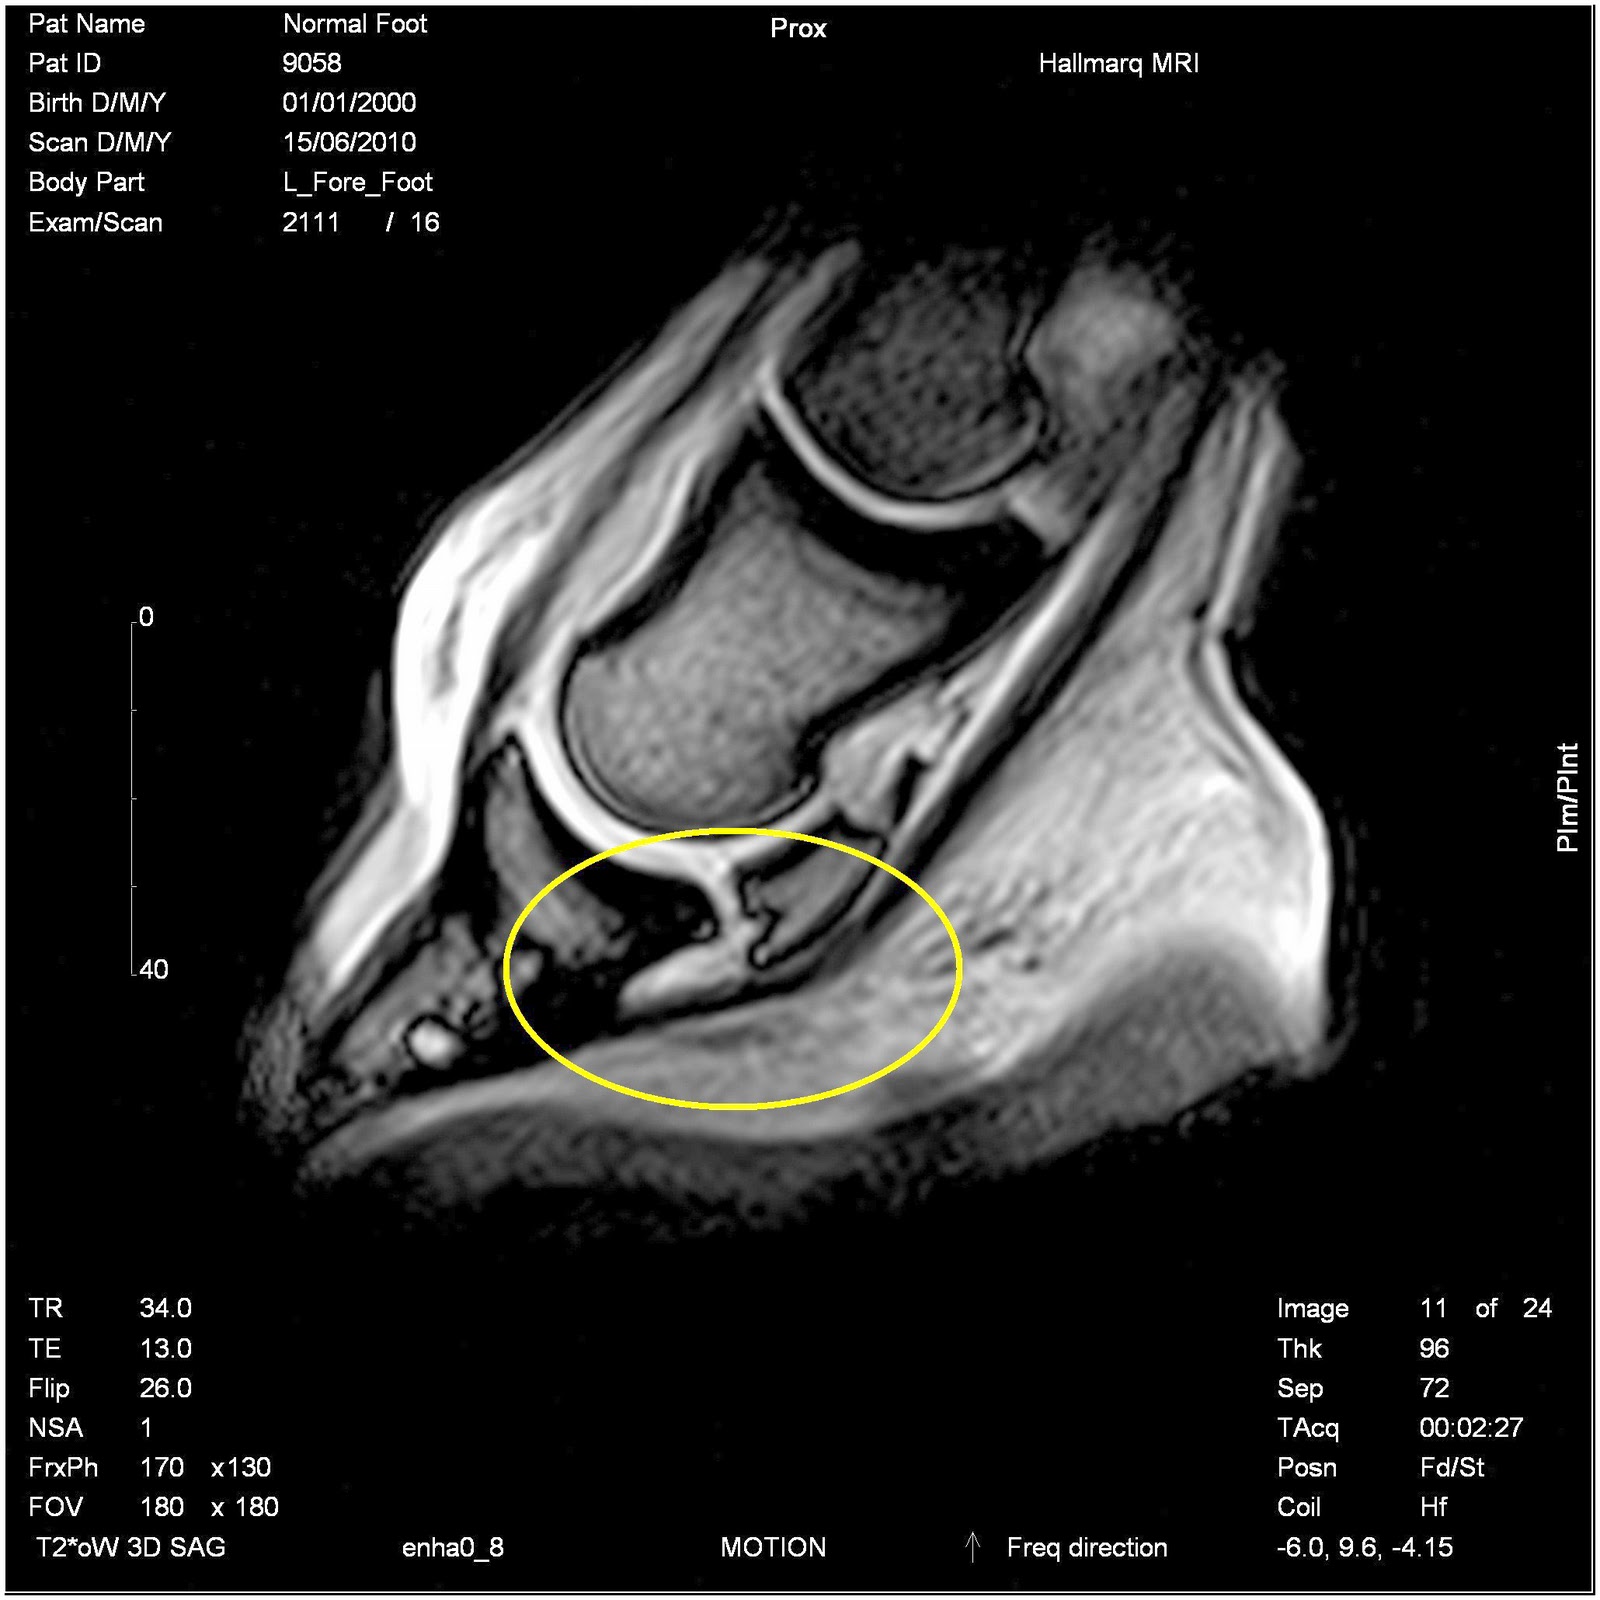

From hoofcare.blogspot.com

Fran Jurga`s Hoofcare + Lameness Hallmarq Veterinary Imaging Presents Dr Sue Dyson's Patient, A Coffin Joint Lameness Treatment Some suggest injecting the corticosteroid into the navicular bursa can have better results. Injecting the coffin joint and/or navicular bursa with corticosteroids to reduce inflammation; Osteoarthritis in the dip joint can be treated with systemic nsaids or chondroprotectants; Many cases of mystery lameness, that may once have been attributed to navicular syndrome, are now thought to be caused by. Two. Coffin Joint Lameness Treatment.